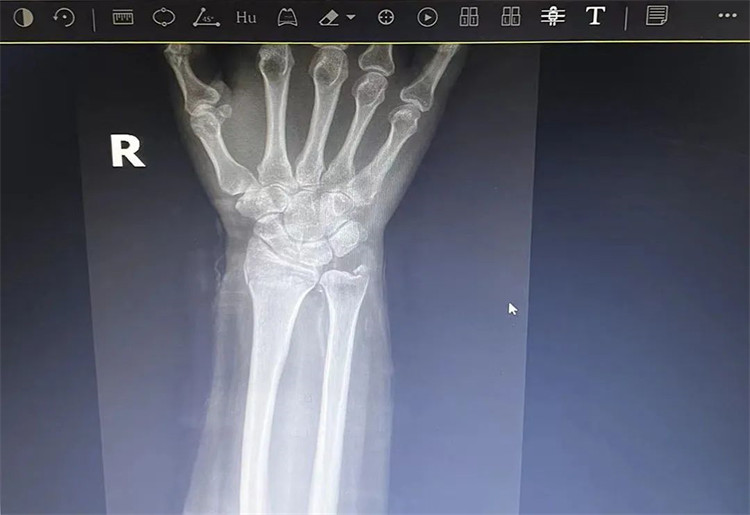

患者老年女性,50多歲,在騎電動車停下時因電動車倒下,右手著地,當(dāng)即感覺,右腕及骶尾部腫痛伴右關(guān)節(jié)畸形、活動受限,急來我院就診。門診醫(yī)師結(jié)合病史、查體及輔助檢查后,診斷為:右橈尺骨遠端骨折、骶尾部挫傷并收入住院部。

患者入院后,中醫(yī)正骨科副主任鄭斌斌,認真查體及分析檢查結(jié)果后,考慮患者老年女性,建議患者采用拔伸牽引、端提、捺正等閉合手法復(fù)位后,行夾板固定,多能獲得較好療效?;颊邚?fù)位固定后,疼痛明顯減輕。避免了手術(shù)帶來的痛苦及手術(shù)開刀所需費用。